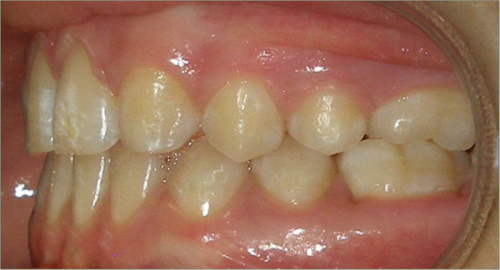

12 year old female:

Diagnosis:

- Missing upper right lateral incisor & lower right cuspid

- Horizontally impacted lower left cuspid

- Peg shaped upper left lateral incisor

Treatment:

- Extraction of impacted lower left cuspid, and peg shaped upper left lateral incisor

- Upper cuspids substituted as laterals

- Full fixed appliances

- 20 months